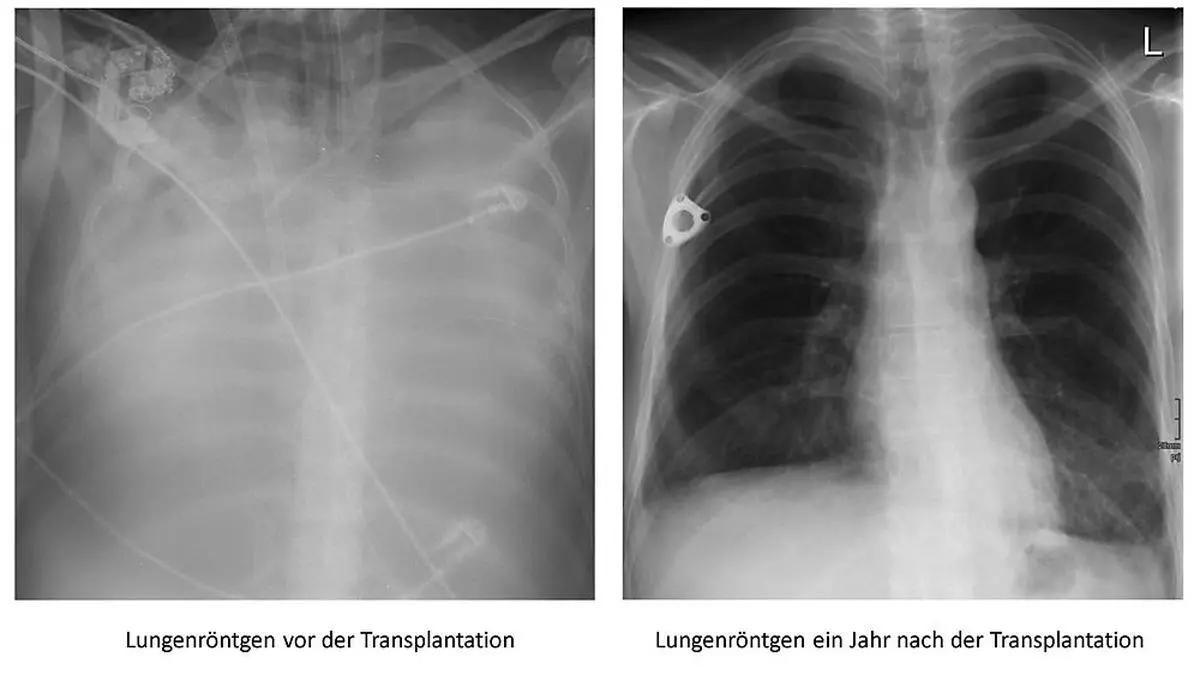

Sabine V. (45) wäre im Vorjahr fast an Corona gestorben. Eine Lungentransplantation im AKH Wien, damals die erste an einer Corona-Erkrankten in Europa, rettete der Kärntnerin das Leben. Erstmals spricht sie über ein „echt hartes Jahr“ und wie sie sich wieder ins Leben gekämpft hat.

Die Lunge der Kärntnerin vor der Operation (links) und danach